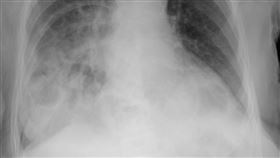

吸菸對人體器官有許多負面影響,包括腦部、肺部和心血管...